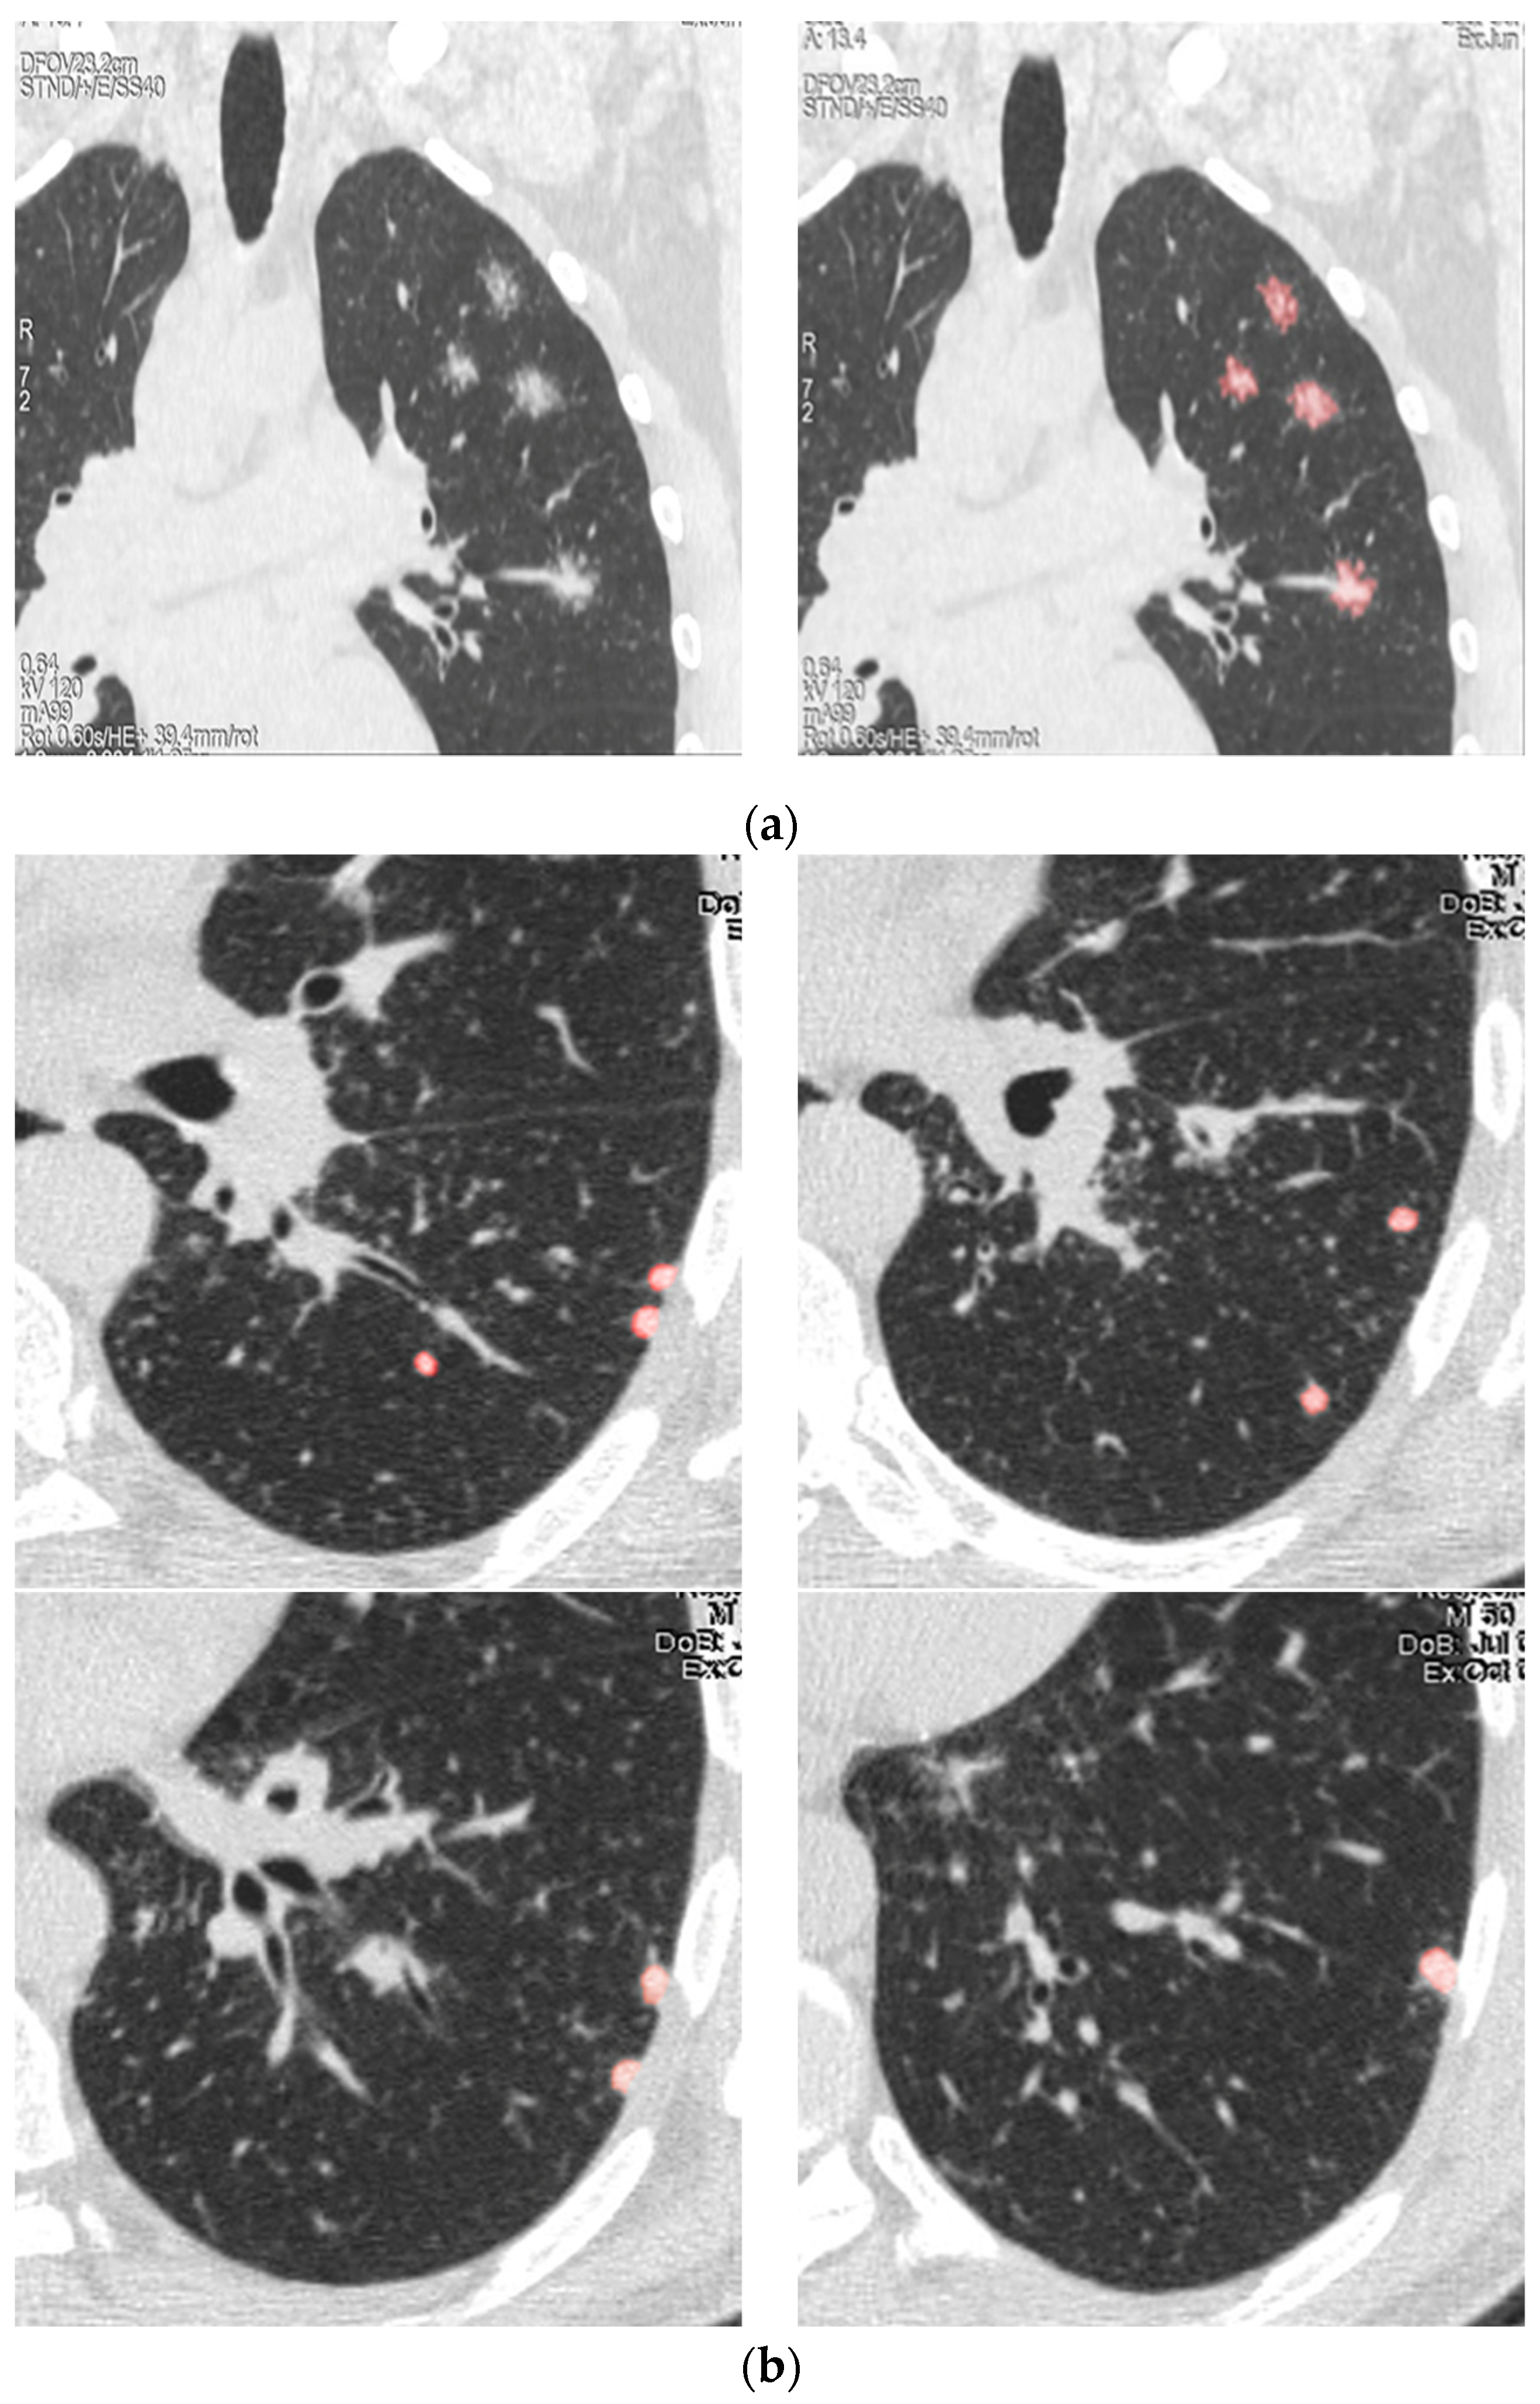

2.2. Follow-Up Testing and Modeling for Predicting the Course of Sarcoidosis

3. Results